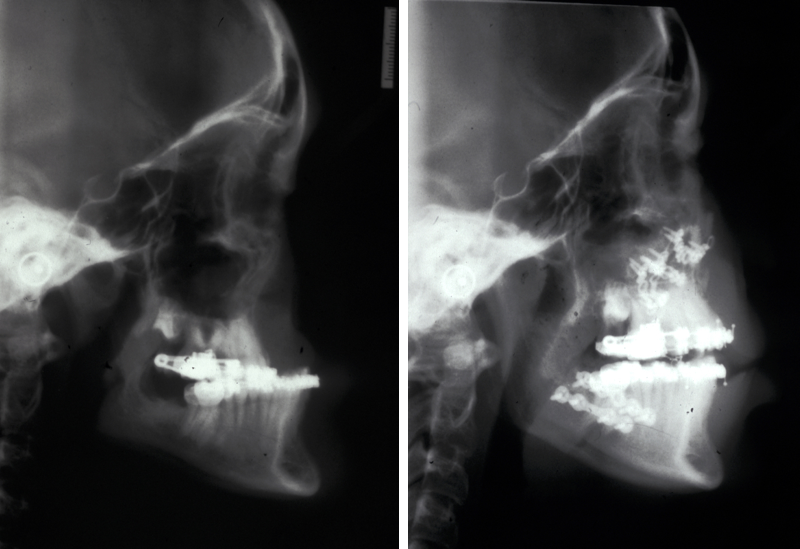

The establishment of the permanent dentition, including guiding of the canines, which have to be exposed in about 15 % of cases, is basically a decision as to whether orthodontic camouflage or orthognathic surgery is indicated. If orthognathic surgery is indicated, standard orthodontic decompensation is carried out and the osteotomies are relatively conservative antero-posterior movements. The chances of advancing a cleft maxilla further than 7 mm without significant relapse is very small (Figure 8, left) and it is customary to balance the movements in the maxilla and the mandible (Figure 8, right) in order to achieve an optimum facial balance and occlusion. Once the maxilla is stabilised, further completion surgery can be carried out.

Figure 8: Left: X-ray image of extreme retrognathia before cleft osteotomy; right: X-ray image after cleft bimaxillary osteotomy showing a good balance of movements.